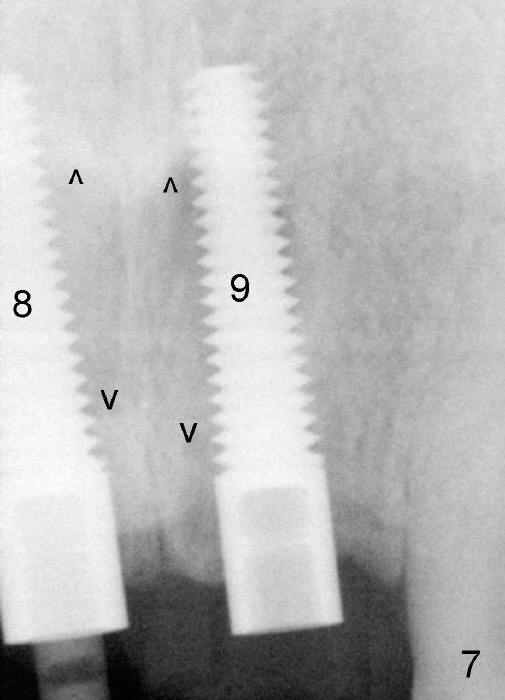

The insertion torque for the implants (4.5x20 mm and 4x20 mm) are 40 and 60 Ncm for #8 and 9, respectively (Fig.7). The stability is probably due to the fact that these two implants are engaged into the two cortical plates of the sockets (arrowheads). Allograft is placed in the mesiodens sockets. Immediate provisionals are fabricated. Fig.8,9 show the provisionals 18 days postop. One of the provisionals (#8) is dislodged 5 weeks postop. Before recementation of the provisional (Fig.10), healthy granulation tissue is found next to the implant (^).